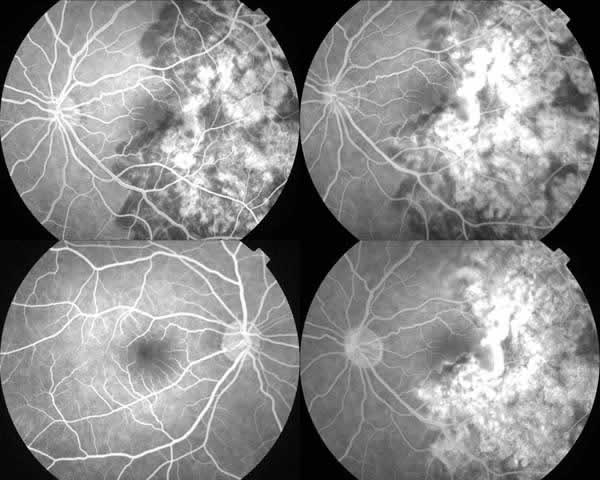

El estudio angiografico mostró lesiones de avance hipofluorescentes en tiempos precoces e hiperfluorescencia tardía sin hallazgos de neovascularizacion subretiniana (fig. 2). Se prescribe tratamiento con corticoides 1mg/kg/día. La analítica y serología descartaron patología orgánica.

Fig. 2: Áreas hipofluorescentes en el angiograma precoz e hiperfluorescentes en tiempos tardíos.

En los sucesivos meses desde el inicio del cuadro se observo una progresión de las lesiones hacia las arcadas temporales superior e inferior, alcanzando progresivamente la zona peripapilar manteniéndose la zona macular preservada dejando como secuelas placas atróficas corioretinianas en su evolución (fig. 3).

Fig. 3: Lesiones pigmentadas con preservación macular. Ojo adelfo sin alteraciones.

Tras 7 años de seguimiento su afectación es unilateral con AV de 1 en ambos ojos, sin signos de neovascularización (fig. 5).

Fig. 5: Evolución a los 7 años.